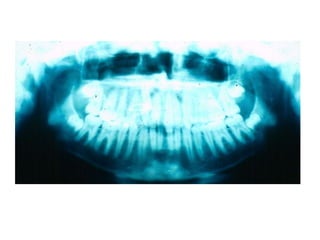

TRANSPOSIÇÃO TOTAL - CANINO COM INCISIVO LATERAL MANOBRAS PARA CORREÇÃO DA ROTA DE ERUPÇÃO